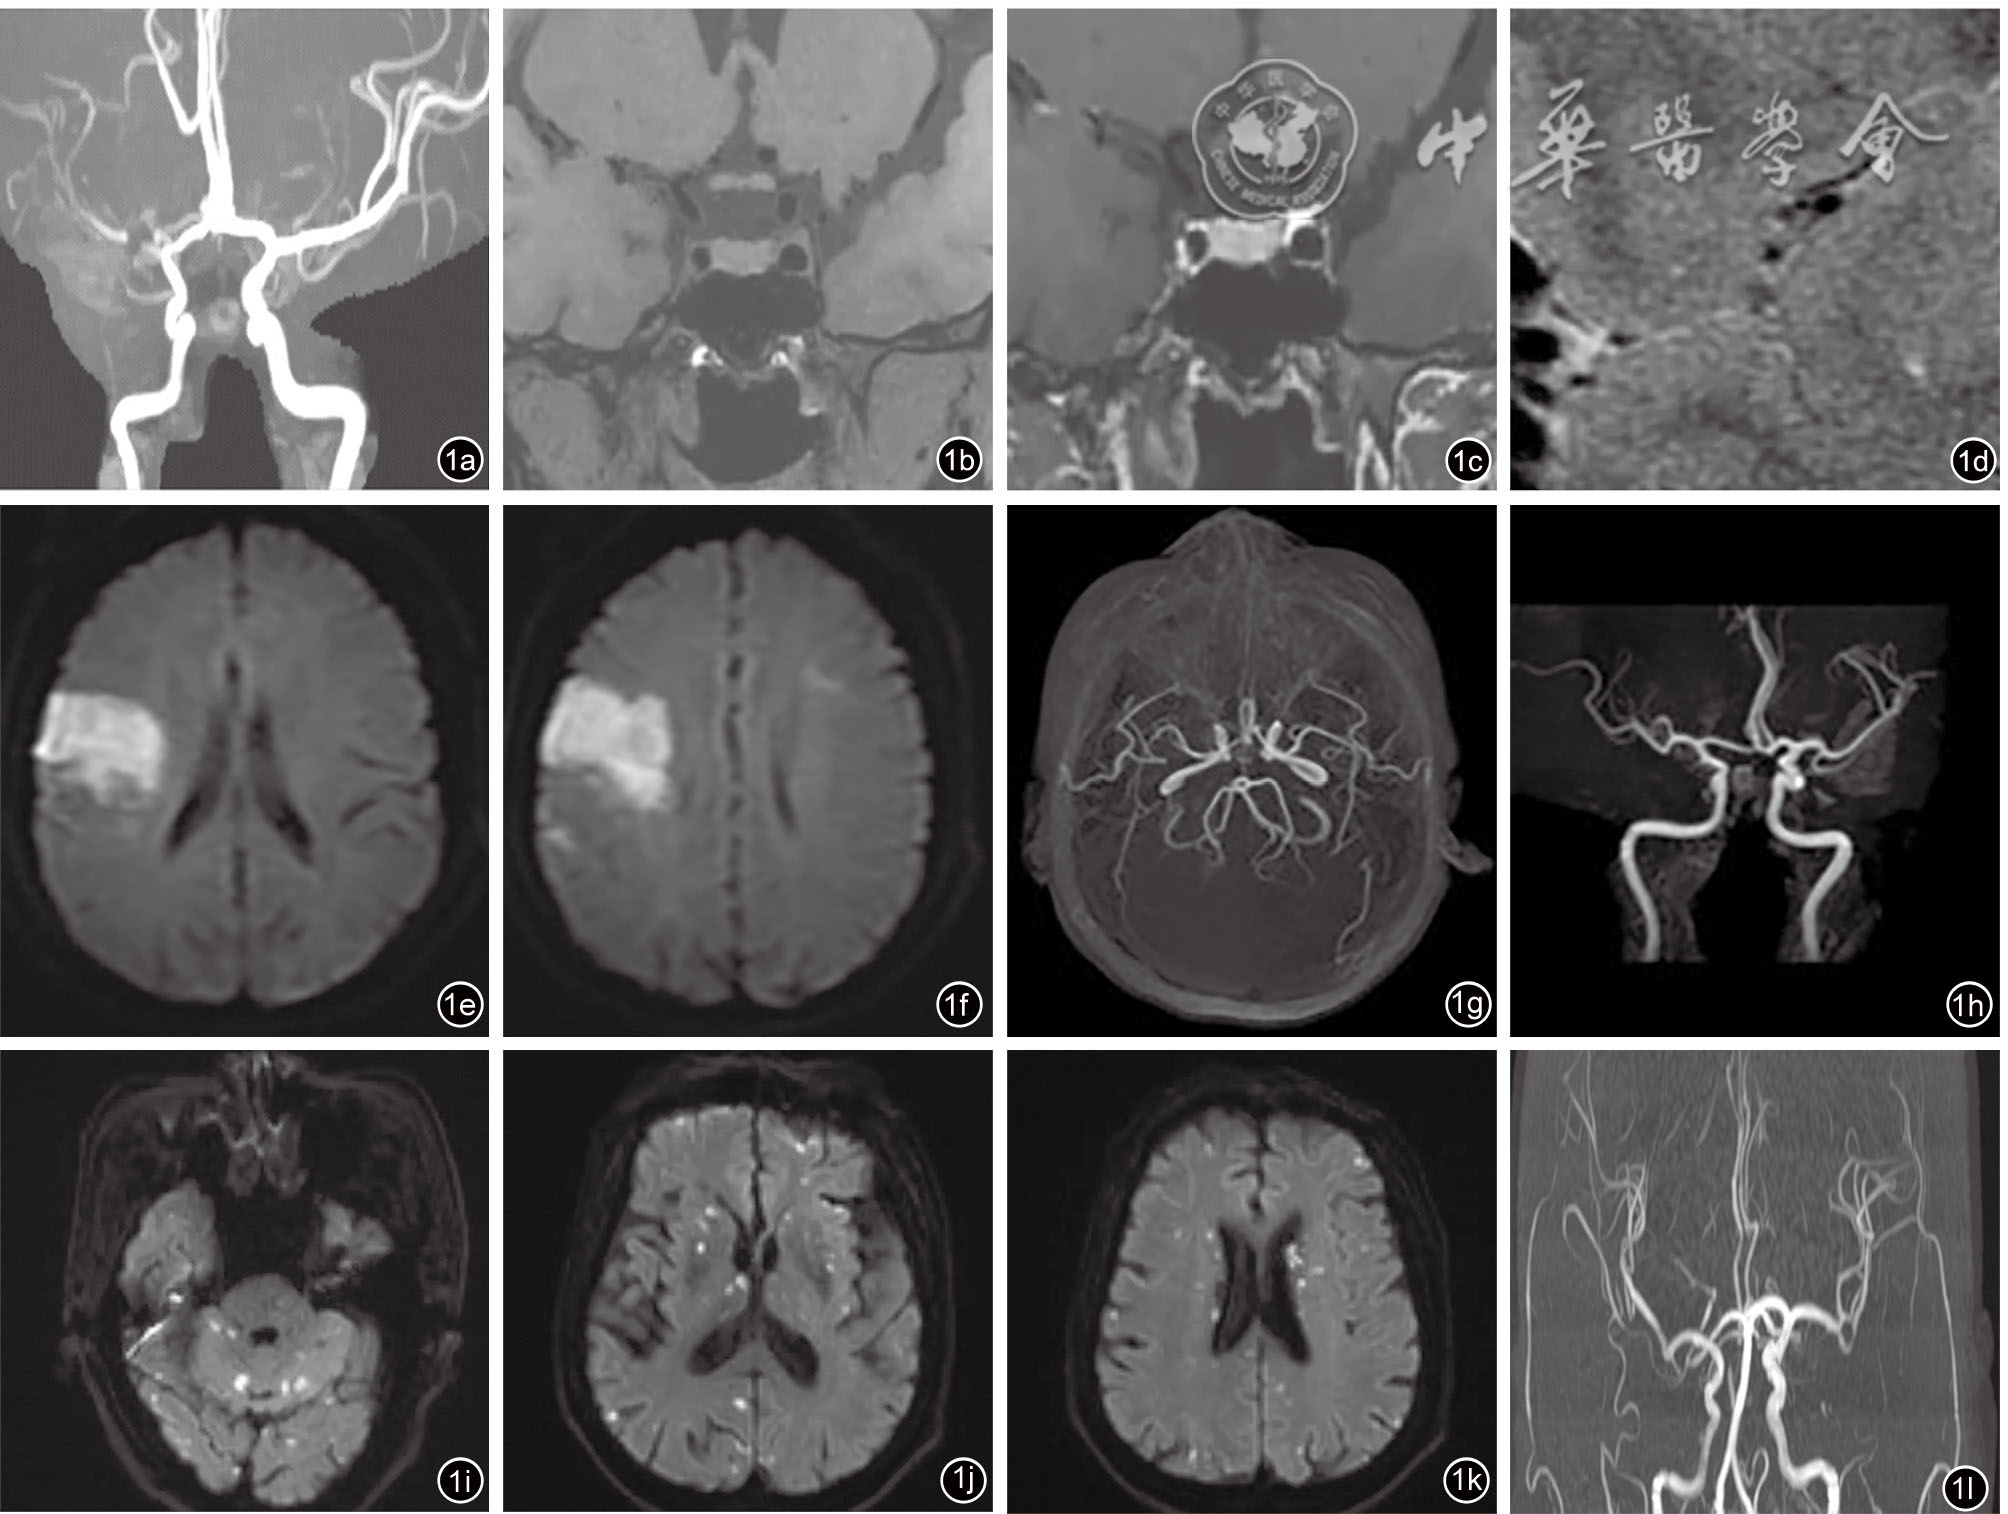

图1 抗磷脂综合征(APS)相关缺血性卒中的影像学图像。图a~d为24岁女性患者,诊断APS,反复一过性左侧肢体无力,头磁共振弥散加权成像(DWI)序列未见高信号,诊断为短暂性脑缺血发作。磁共振血管造影(MRA;图a)可见右侧大脑中动脉M1段中段重度狭窄,高分辨磁共振脑血管成像(图b~d)可见右侧大脑中动脉M1段偏心性狭窄,狭窄处可见动脉粥样硬化斑块,局部明显硬化。图e~h为38岁女性患者,诊断为系统性红斑狼疮,继发性APS;头磁共振成像(MRI)侧脑室层面(图e)及半卵圆中心层面(图f)提示右侧额叶见斑片状DWI高信号,左侧额叶白质内见小片状DWI稍高信号,提示亚急性多发性脑梗死;MRA(俯视图g、正视图h)显示颅内动脉未见明显狭窄;经胸超声心动可见二尖瓣前叶瓣尖左心房面强回声团块影,大小为6 mm×4 mm,提示Libman-Sacks赘生物可能性大;考虑患者卒中病因为APS相关心脏瓣膜病所致的心源性栓塞。图i~l为71岁男性患者,诊断为APS。头MRI(图i~k)显示双侧大脑皮质及皮质下、基底节、侧脑室旁、脑干及小脑可见弥漫不均匀分布的点状、小结节状DWI高信号,考虑多发性急性或亚急性脑梗死;MRA(图l)未见颅内动脉狭窄;心脏相关检查未发现心房颤动及瓣膜赘生物等心脏病变,提示高凝机制所致缺血性卒中可能性大